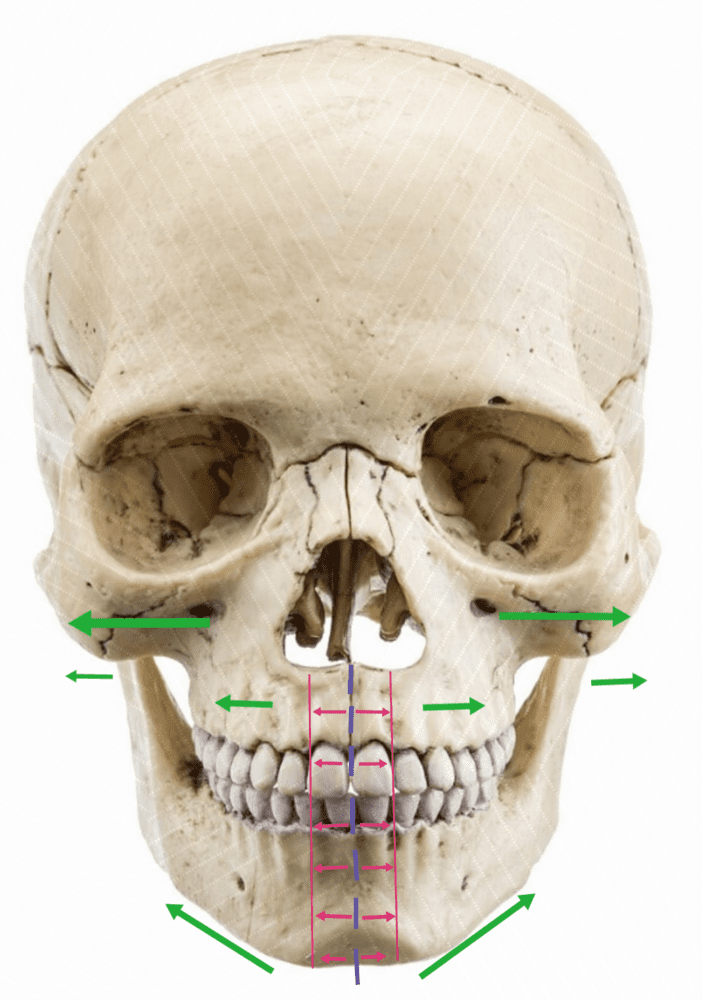

Expands the width of maxilla, mouth, nasal base, and zygomatics expansion. You would need corticopuncture done so you can expand with MSDO at the same rate.

MSDO expands the lower jaw (particularly chin). The lower jaw can follow only so much the forced expansion the maxilla is subjected to from the MSE. This, in combination with the MSE can widen the chin, expand the palate, increase the lateral protrusion of the zygos

Expands the width of maxilla, mouth, nasal base, and zygomatics expansion. You would need corticopuncture done so you can expand with MSDO at the same rate.

MSE Results (Cheekbones width, maxilla).

10mm of MSE equals =

8.4 mm - cheekbones width (0.84mm gain for every milimeter of MSE expansion)

1.2 mm - Maxilla forward growth (upper and lower)

10mm of MSE equals =

8.4 mm - cheekbones width (0.84mm gain for every milimeter of MSE expansion)

1.2 mm - Maxilla forward growth (upper and lower)

MSDO expands the lower jaw (particularly chin). The lower jaw can follow only so much the forced expansion the maxilla is subjected to from the MSE. This, in combination with the MSE can widen the chin, expand the palate, increase the lateral protrusion of the zygos